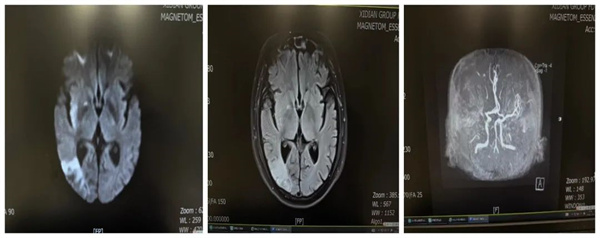

進(jìn)行CT檢查后,閆先生頭顱未見明顯出血,血常規(guī)、凝血系列未見明顯異常。顱腦DWI:右側(cè)額葉、半卵圓中心、基底節(jié)區(qū)、側(cè)腦室旁多發(fā)彌散受限信號(hào),顱腦MRA:右側(cè)大腦中動(dòng)脈閉塞,因右側(cè)枕葉病灶Flair已顯影,頭顱DWI-Flair無錯(cuò)配。郭芳住院醫(yī)師評(píng)估無靜脈溶栓指征,頭顱MRA示右側(cè)大腦中動(dòng)脈主干開口段閉塞,因核心梗死區(qū)與血管供血區(qū)不匹配,有急診血管開通手術(shù)指征,請(qǐng)示上級(jí)主任醫(yī)師后,建議行急診腦血管造影術(shù)+備血管開通術(shù)。

林濤主任立即在局部浸潤(rùn)麻醉下為閆先生行腦血管造影術(shù)+血管開通術(shù),術(shù)后造影見右側(cè)大腦中動(dòng)M1段閉塞,給予球囊擴(kuò)張+支架植入,右側(cè)大腦中動(dòng)脈血流恢復(fù),顯影良好。術(shù)后給予閆先生吸氧、心電監(jiān)護(hù)、抗血小板聚集、穩(wěn)定板塊、促進(jìn)側(cè)支循環(huán)、清除氧自由基、營(yíng)養(yǎng)神經(jīng)以及康復(fù)理療等治療。